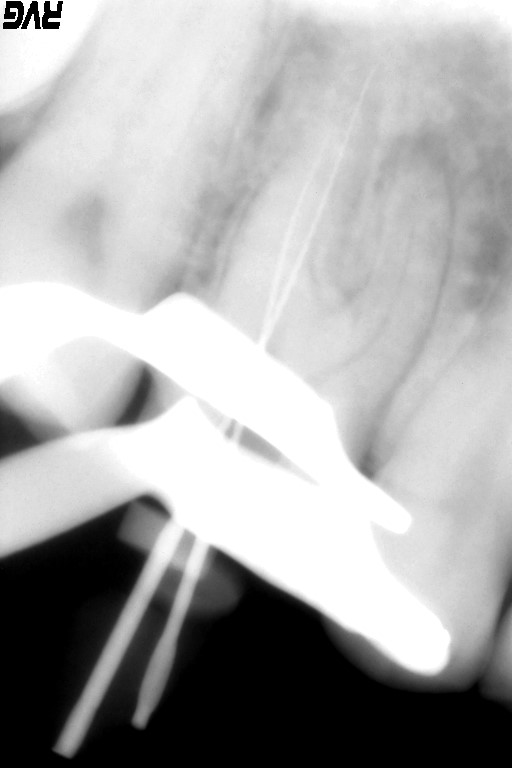

根尖までの長さや根尖孔の太さを確認するためにファイルを入れてレントゲン撮影を行います。

根管形成が終わり、根管洗浄を十分に行い、バイオセラミックによる根管充填を行ないました。

根尖部よりバイオセラミックが出ているが、臨床的には何も問題はありません。この語、骨が再生されるまでには数ヶ月時間かかります。